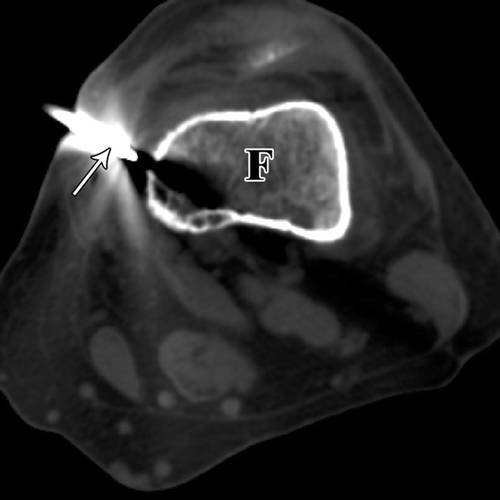

5 / 20岁女性桡骨内软骨瘤。

前臂的CT图像显示11号针头(箭头),桡骨(星号)。小心不要穿过骨间膜。